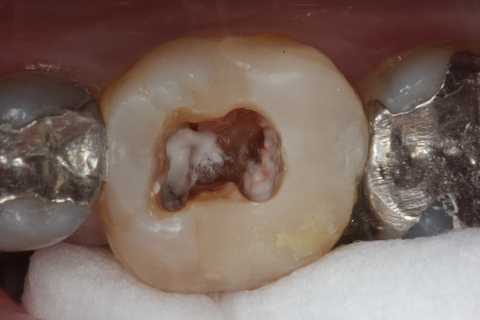

残根上のCR8 2025.10.28

伝説の根管治療法4(Per+GA、3MIX+α-TCP) 2025.10.27